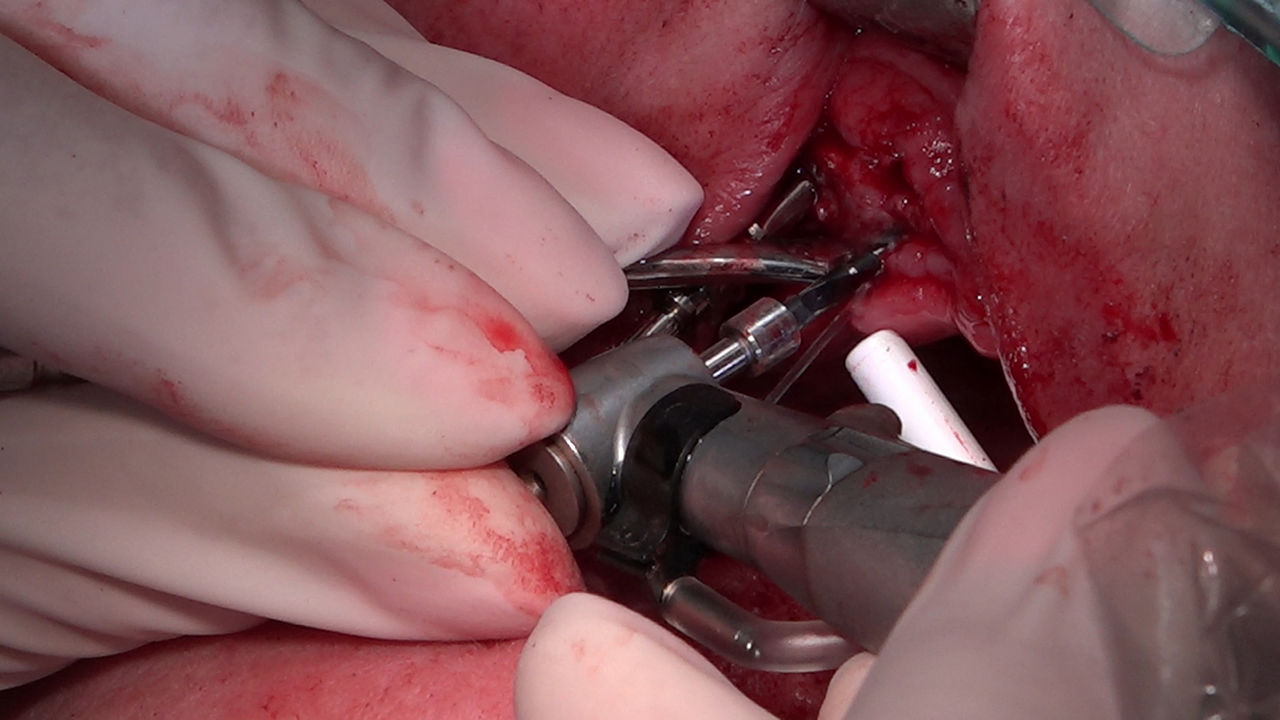

Practiculum Implantologii to szkolenie dla adeptów implantologii zorientowane na praktyczne opanowanie procedur zabiegowych i wprowadzenie implantologii do własnej praktyki. Dla Kursantów Grupy A, X Sezonu, 9 Sesja stanowiła ostateczny sprawdzian umiejętności zabiegowych zdobytych podczas procedur wykonywanych w trakcie szkolenia pod kierunkiem dr n.med. Violetty Szycik i dr Małgorzaty Piotrowskiej. Zobacz więcej na: www.practiculum.pl